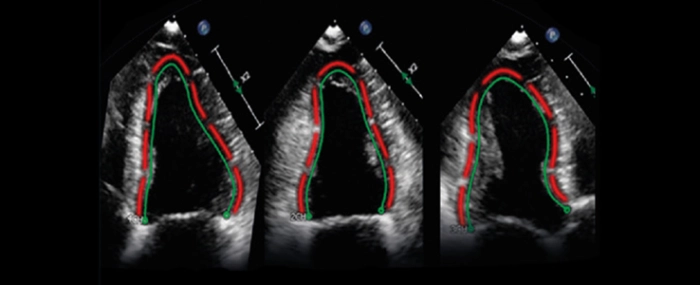

© TomTec

Royal Philips has signed an agreement to acquire TomTec Imaging Systems GmbH, a provider of intelligent image analysis software, especially for diagnostic ultrasound.

Headquartered in Munich, Germany, TomTec "will strengthen Philips’ leadership position in cardiac ultrasound, and support the company’s further expansion in other clinical areas, such as obstetrics and gynecology (OB/GYN)". Completion of the transaction is expected immediately. Financial details were not disclosed.